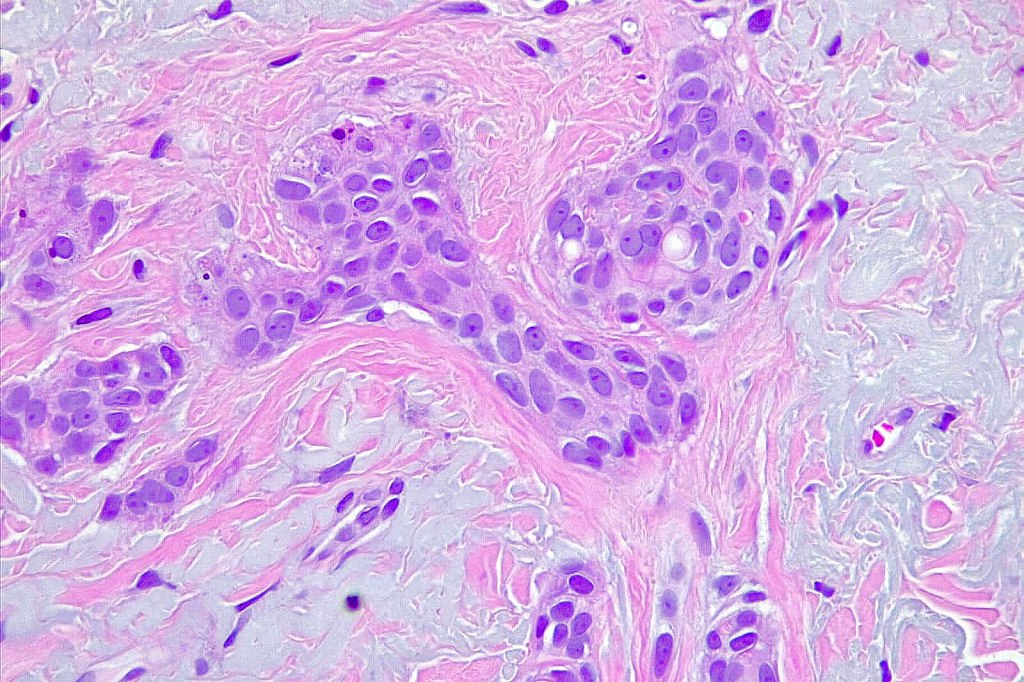

Histological features

•Dermal lesion composed of epithelial stands & ducts dispersed in a fibrous stroma

•Tadpole configuration- ducts with epithelial strands

Intracytoplasmic lumina

•Absence of pleomorphism or mitotic activity